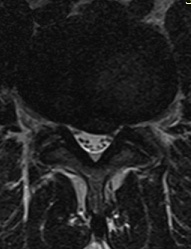

Sagittal T2 weighted image of the lumbar spine. Small to medium sized disc protrusion at L4-5.

Axial T2 weighted image of the lumbar spine. The same L4-5 disc protrusion is potentially compromising the descending left L5 nerve root.